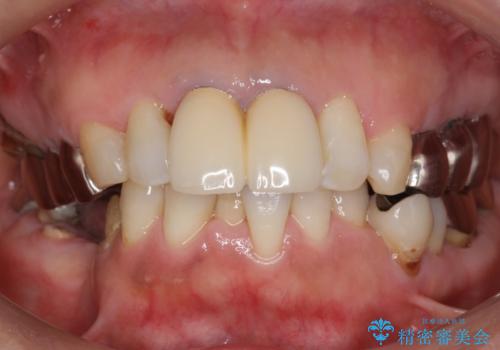

- 奥歯のインプラントをご希望され、来院された患者様です。

骨が薄いため、他院ではインプラントできないと言われたとの事でした。

精査したところ、右下4の根尖病変及び右下5の欠損を認め、右下6は残根となり保存不可能な状態でした。

保存不可能な歯を抜去後、インプラント治療と根管治療を行いました。